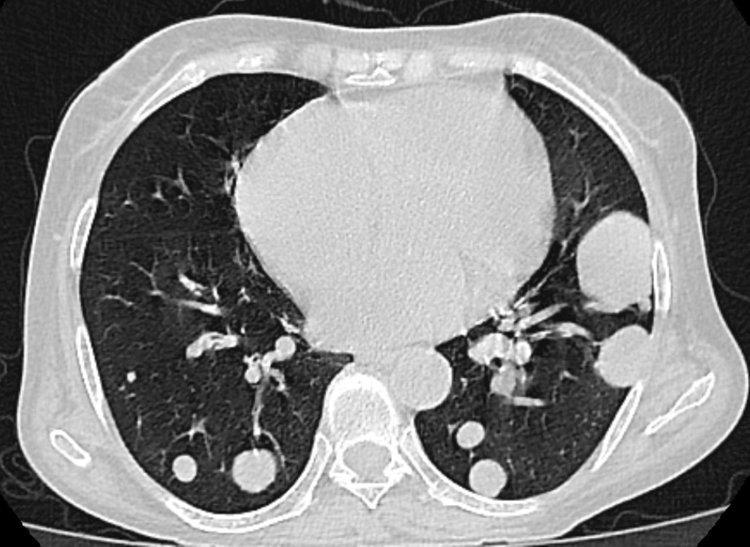

去年的體檢報告上,顯示有肺部結節,醫生叮囑他要隔段時間來複查,但他沒放在心上,覺得自己身體沒問題。

近段時間被頻繁的咳嗽、胸痛困擾,劉叔只好去了醫院,結果發現之前的結節變大了,醫生便趕緊給他安排了手術,病理顯示浸潤性腺癌,好在發現及時並處理了。

結節其實是人體內體積較小的一種腫物,可發生於人體的任何部位,由於如今的CT分辨率越來越高,因此結節的檢出率也變高了。

上海市胸科醫院住院醫師李博斐介紹:根據結節的位置不同,有甲狀腺結節、肺結節、乳腺結節等不同分類,多數結節是良性的,只有少數是惡性的。